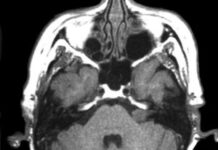

Что показывает МРТ черепно-мозговых нервов?

МРТ черепно-мозговых нервов очень частая и востребованная услуга. Стоит отметить, что ее проводят специально для того чтобы визуально посмотреть патологии и разные дисфункции. Нервная...